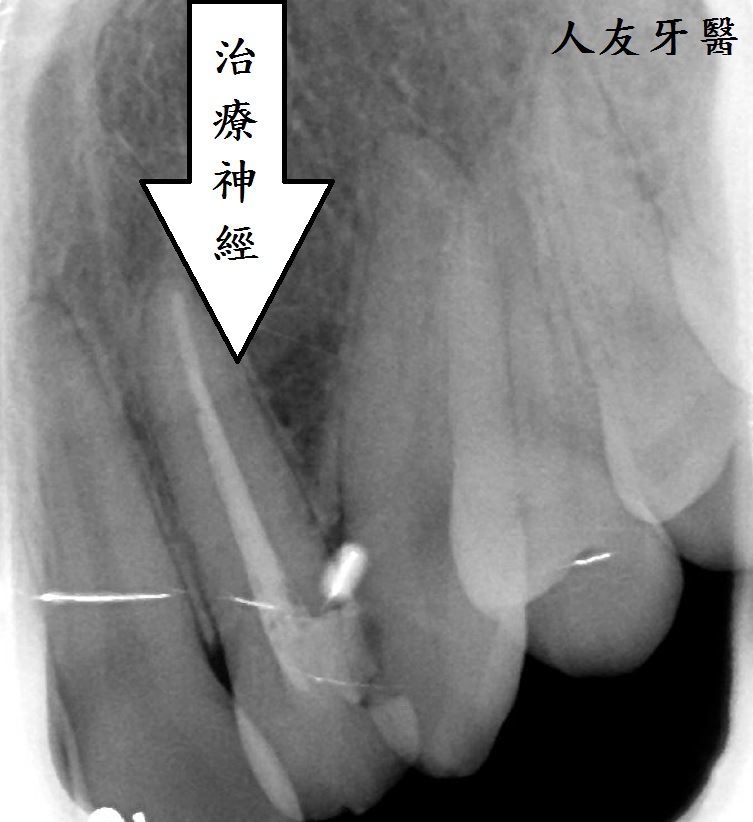

而左側門牙根尖有一個病變,醫師透過根管治療的方式把牙根深層的細菌清除乾淨,放入柱心補強,最後再搭配牙套保護.